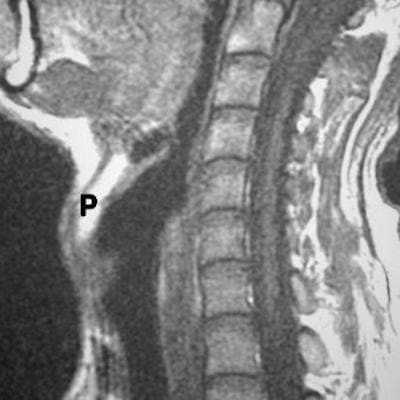

Плоскоклеточный рак гортаноглотки наиболее часто включает грушевидные синусы. Раки, которые возникают в этом месте, как правило, долго не проявляются и очень агрессивные. Они прорастают в глубокие пространства и сразу поражают многочисленные лимфатические узлы. Опухоль может прорастать хрящ и даже гортань. При МРТ мягких тканей правильная оценка характера роста плоскоклеточного рака гортаноглотки очень важно для стадирования процесса и хирургической тактики лечения.

Что касается глубинных структур, особое внимание при МРТ мягких тканей шеи следует уделить распространению опухоли на превертебральное пространство. Инвазия глубокой фасции шеи, длинных мышц шеи, или самого позвоночника, определяемые при МРТ мягких тканей шеи, ставят вопрос об обширной операции. Кроме того, поражение сонной артерии ставит вопрос о резектабельности. Некоторые хирурги считают, что если опухоль по данным МРТ мягких тканей шеи охватывает меньше 50% сонной артерии она может быть от нее отделена. Вероятность невозможности удаления опухоли заметно увеличивается, когда по данным МРТ мягких тканей шеи она окружает более 75% сонной артерии. Вовлечение в процесс жевательного пространства может происходить с ротоглотки. Вовлечение жевательного пространства должно насторожить в плане прорастания основания черепа, особенно, через овальное окно и/или вдоль крылонебной ямки. Другие пути распространения через основание черепа идут вдоль сонного канала, через яремное отверстие, и евстахиеву трубку